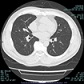

最新の技術により以前より低被ばくで全身の横断面像が撮影でき、再構成することにより冠状断面像、矢状断面像も観察できます。

胸部横断面像 胸部冠状断面像 胸部肋骨立体像